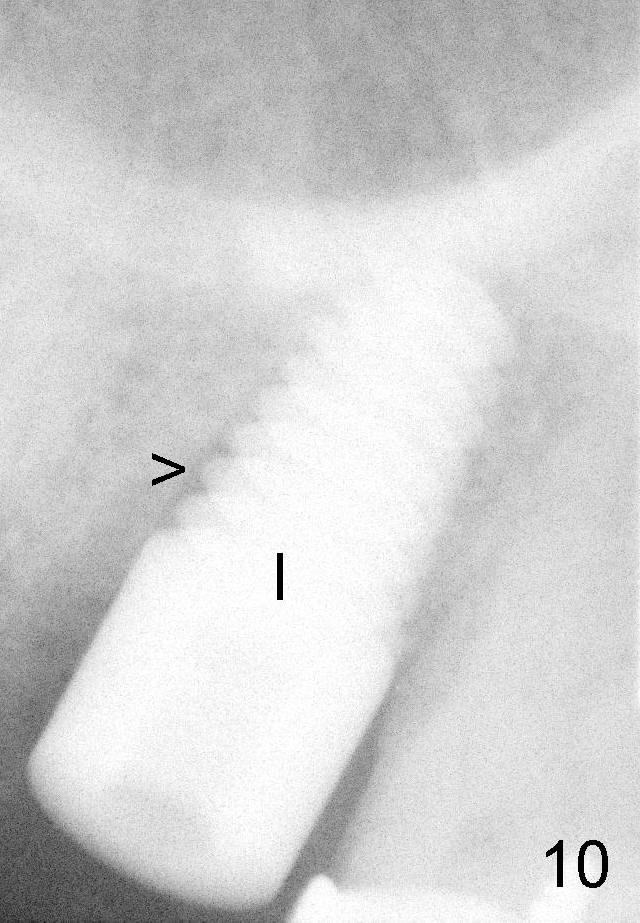

Fig.10: Implant (I, 6x14 mm); a small gap mesially (>), which disappears 11 months postop (Fig.11).